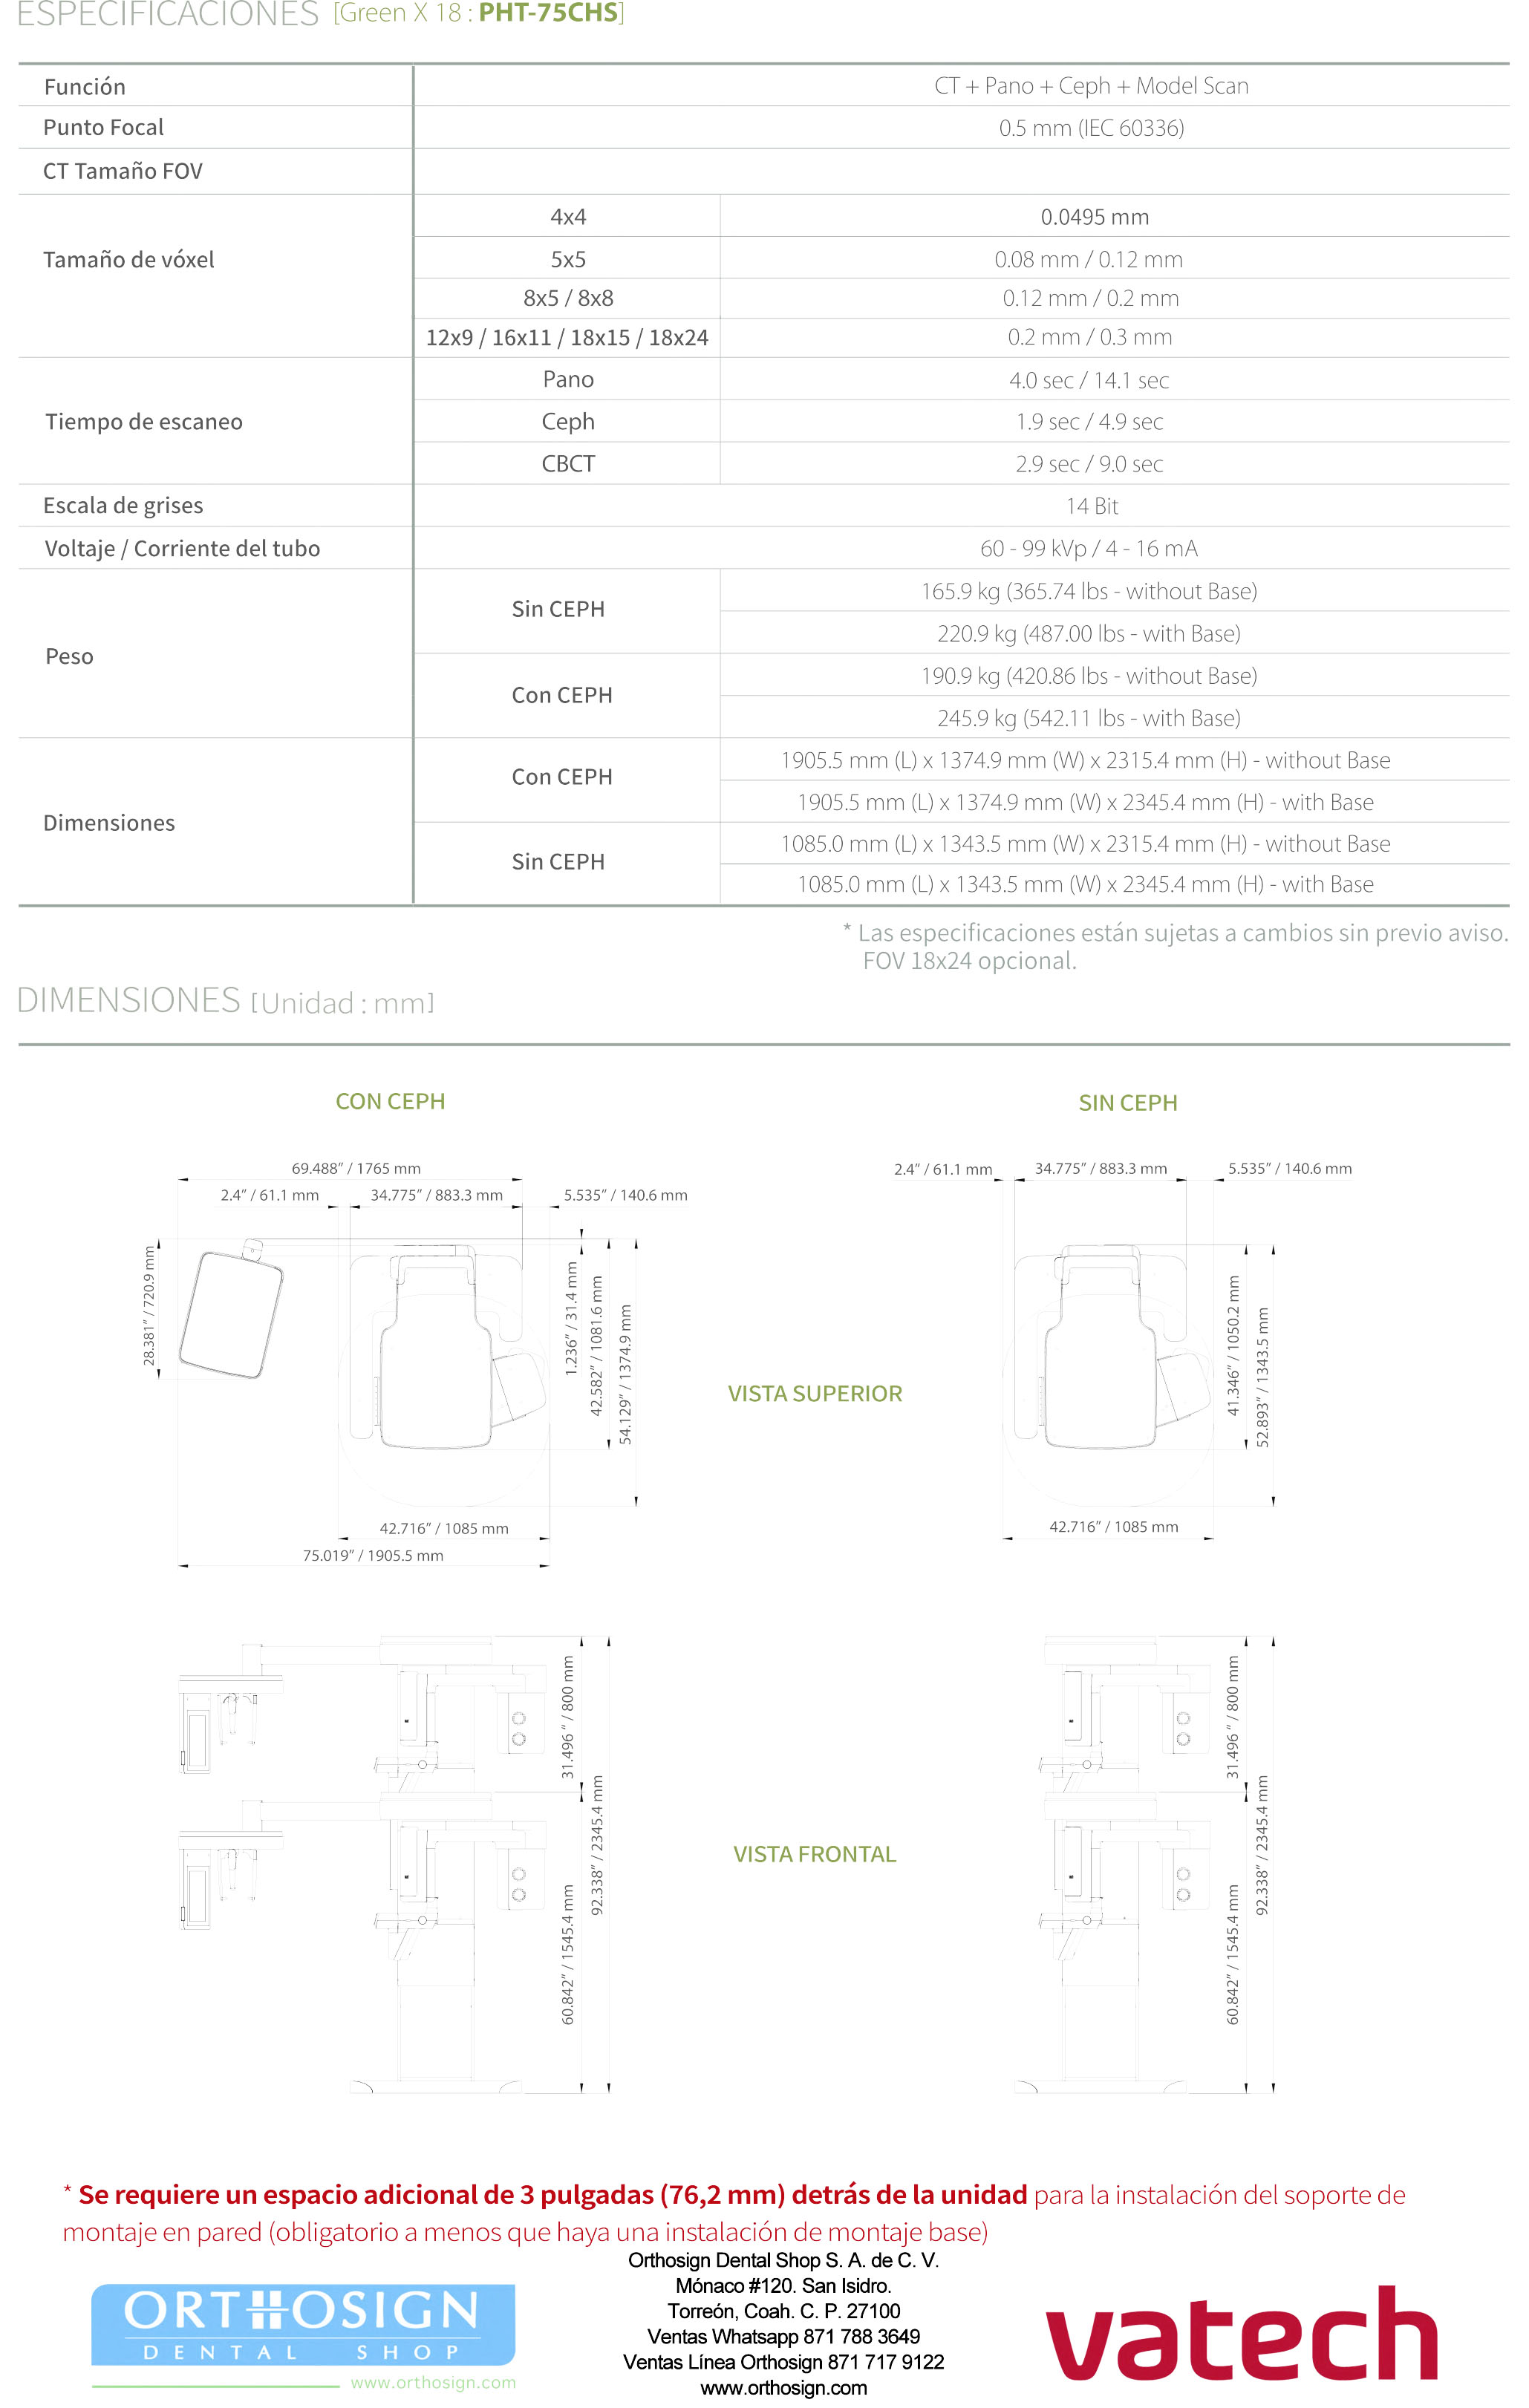

Tomógrafo 3D Dental con Ortopantomógrafo y Cefalostato.

- CBCT, Cone Beam Computer Tomography. Imágenes en 3D de 18 x 24 cm.

- FOV hasta 24 x 15 cm (Double Scan). Sensor 18 x 15 cm.

- Radiografía Panorámica (ortopantomografía).

- Radiografía Lateral de Cráneo (Ceph Rápido de 1. 9 Segundos).

- Radiografía de ATM.

- Radiografía de Senos Paranasales.

- Radiografía de Aleta de Mordida.

- Radiografía Carpal.

- Radiografía AP y PA.

- Radiografía Waters.

- Radiografía Submentovertebral.